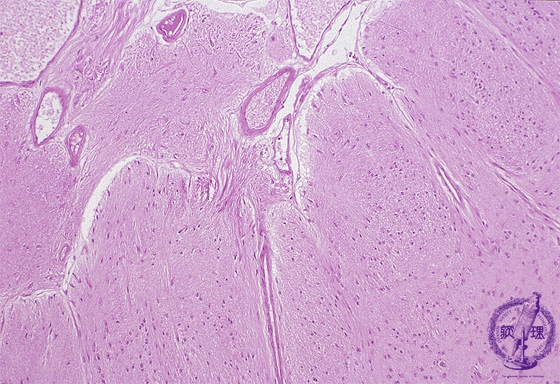

- (8)Glioma(Astrocytoma)

Microscopic findings (H.E. low magnification): Fibrillary astrocytoma demonstrated a diffuse proliferation of tumor cells with small oval nuclei and fine neurites. Nuclear polymorphism was not prominent. Tumor cells invaded the subarachnoidal space in left upper of the figure.